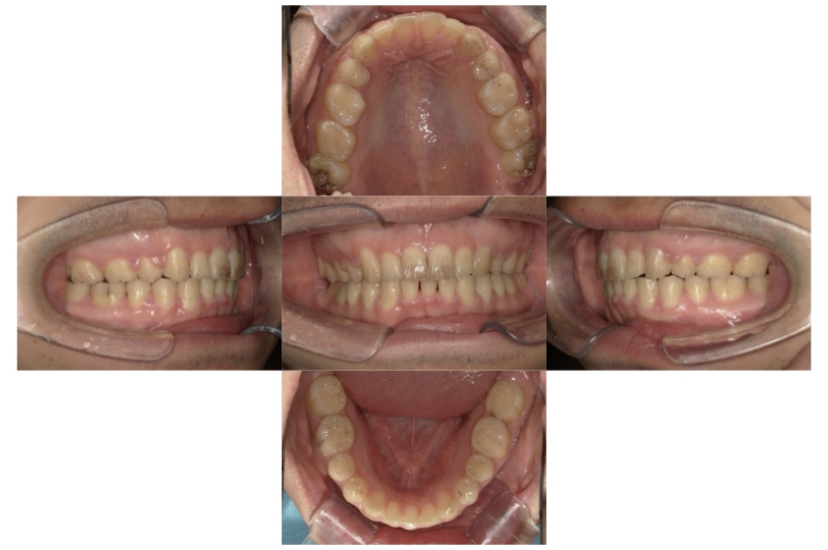

BEFORE

AFTER

上下顎叢生(上下の前歯のガタガタ)のケースです。

装置はラビアル(上下表側)で、上下顎の小臼歯を4本抜歯を行っています。抜歯したスペースを使って、上下の前歯の後方移動と叢生(ガタガタ)の改善を行っています。

主訴 歯並びが悪く、舌を噛んでしまうのを治したい。

年齢・性別 27歳 男性

お住まいの地域 東京都大田区

治療方針 抜歯スペースを利用して上下前歯の叢生(ガタガタ)の改善

抜歯部位 上下顎左右第一小臼歯

使用装置 ラビアル(上下表側)、顎間ゴム

治療期間 3年1か月

治療回数 30回